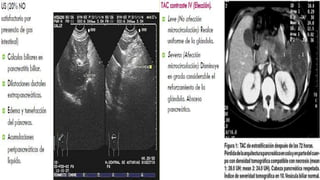

1985 por Balthazar

Clasifican las PA en cinco grados (A-B-C-D-E) en

función al tamaño, contorno, densidad y

existencia de enfermedad inflamatoria

peripancreática con o sin la presencia de una o

más colecciones líquidas.

Se considera necrosis pancreática el área

glándular que no realza después de la

administración de contraste endovenoso. Se

clasificó según el porcentaje de la glándula

afectada en tres grupos: 1) Menor al 30%.

2) Menor al 50%.

3) Mayor o igual al 50%

1985 por Balthazar Clasificanlas PA en cinco grados (A-B-C-D-E) en función al tamaño, contorno, densidad y existencia de enfermedad inflamatoria peripancreática con o sin la presencia de una o más colecciones líquidas. Se considera necrosis pancreática el área glándular que no realza después de la administración de contraste endovenoso. Se clasificó según el porcentaje de la glándula afectada en tres grupos: 1) Menor al 30%. 2) Menor al 50%. 3) Mayor o igual al 50%